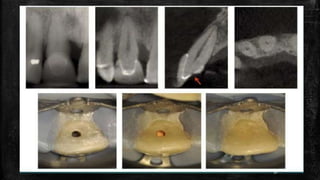

Preoperative view of tooth #19 in

a 20-year-old woman.

(A) The deroofing problem. The likely bur used by the

referring general dentist is a 56 carbide; one of the most

popular burs in dentistry,6 it is possibly the most

iatrogenic instrument in modern medicine. Red arrow

delineates the typical gouging. (B) Postoperative view

provided by the endodontist. Blue arrow indicates the

grossly excessive dentin removal of pericervical dentin

(PCD). This serious gouging is typical of round bur access.

Yellow arrow indicates the large canal flaring with

unacceptable dentin removal (blind funneling). (C) Green

circle highlights worsening lesion on mesial root ends.